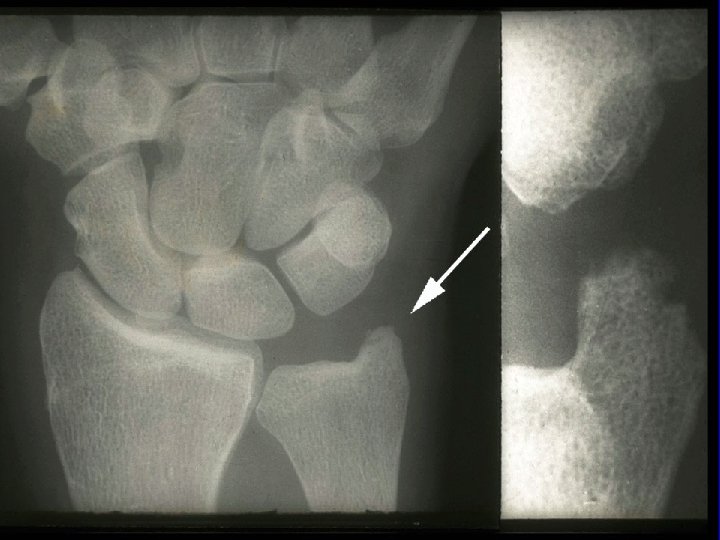

Baseline Evaluation of Patients · Radiography - Wrist and hands - Feet - Other symptomatic joints

Sharp Scores of Radiographic Progression Erosion scores · 17 joints of each hand/wrist · 6 joints of each forefoot · Scale: 0– 5; Total score: 0– 230 Joint space narrowing (JSN) scores · 16 joints of each hand/wrist · 5 joints of each forefoot · Scale: 0– 4; Total score: 0– 168 Total Sharp score · Add erosion and JSN scores · Total score: 0– 398 Sharp JT, et al. Arthritis Rheum. 1985; 28: 1326– 1335 van der Heijde DM, et al. J Rheumatol. 1995; 22: 1792– 1796.

Prognostic Markers in RA · Definitive Markers - Subcutaneous nodules - Detection of erosions on x-ray

Joint Erosions Occur Early in RA Maximum % Joints Affected · Up to 93% of patients with <2 years of RA may have radiographic abnormalities · Erosions can be detected by MRI within 4 months of RA onset Hand MTP All · Rate of progression is significantly more rapid in the first year than in the second and third years Year Fuchs HA et al. J Rheumatol. 1989; 16: 585 -591. Mc. Queen FM et al. Ann Rheum Dis. 1998; 57: 350 -356. van der Heijde DM et al. J Rheumatol. 1995; 22: 1792 -1796.